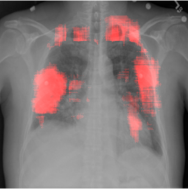

4.2.1 Cardiomegaly Localization

The localization of abnormalities in cardiomegaly examples are shown in Fig. 7. Here, of the image area is shown which has the highest sensitivity. It can be observed from the figures that the network is indeed most sensitive to the region where the heart is larger than a normal heart. We have performed this experiment on cardiomegaly and normal images and found this localization to be consistent for most examples. There is not much functional difference between a normal and cardiomegaly example other than the fact that the heart in cardiomegaly is larger than a normal heart. Given the fact that the normal images could also have various size of heart depending on the age or physical attributes of a patient, we found this level of localization sensitivity to be remarkable. Also interesting is the fact that the standard rule based features like CTR and CTAR take into account the relative size of heart and lung to determine if there is cardiomegaly present or not. In the DCN localization experiment, we see counter-intuitively that most of the signals contributing to the softmax score are coming from the heart only. This means that there are characteristic features in the shape of the heart and its surrounding regions that alone is sufficient to detect cardiomegaly. The lung and its relative size are probably less important features when trying to detect cardiomegaly. This observation is counterintuitive and needs to be explored further in future work.

8 Additional Examples of Localization

In this section we show more examples of localization. Few localization samples are shown in Fig. 11. It can be observed that, in the CXRs with Cardiomegaly (Fig. 11(a) and (b)) a fine localization around the heart is observed. In the normal CXRs (Fig. 11(c) and (d)) such localization is not observed. Rather the lowest probabilities are spread out in the CXR image. It is interesting to note that, the localization algorithm gets low probability where the heart is enlarged during cardiomegaly, but the proportion is small compared to the localization in other areas of normal CXRs. In order to observe the performance of the heat map we computed histograms of heat maps of each of the 100 CXRs in the test set for Cardiomegaly detection and average histograms are shown in Fig. 11(e) and (f) for CXRs with Cardiomegaly and normal CXRs, respectively. It is to be noted that, the histograms include both success and failure cases. It can be observed that, for CXRs with Cardiomegaly the classifier is highly sensitive toward Cardiomegaly detection even under occlusion. This indicates that, the classifier primarily looks for local features in a CXR instead of some feature that is spread out in the entire CXR. However, the classifier is not sensitive toward normal CXRs under occlusion. Rather, the probabilities are spread out in the probability spectrum. After that, we analyzed the failure cases where the classifier is unable to classify the image correctly. Two such examples of failure cases are shown in Fig. 12. The localized CXR shown in Fig. 12(a) contains Cardiomegaly whereas the classifier detects it as normal. However, the localization shows that it localizes around heart quite well despite the in accurate classification. On the other hand, Fig. 12(b) shows an example of normal image which has been classified as Cardiomegaly by the classifier. There is stronger localization around the hear that that is observed for normal images as in Fig. 11(c) and (d), however, like those images the localization is spread out.